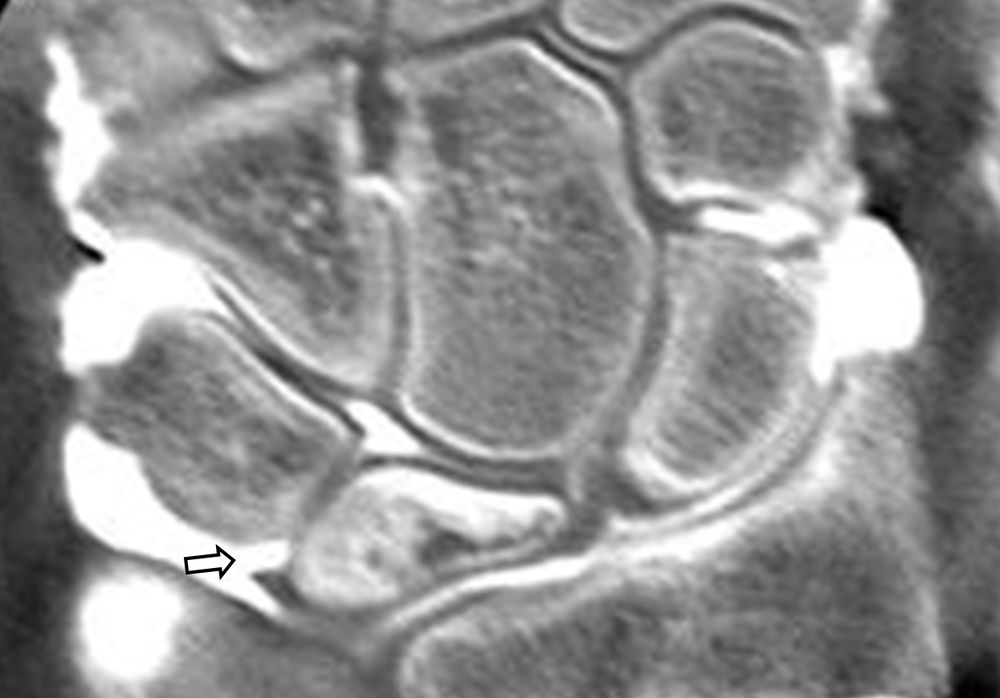

Είναι μια ελάχιστα επεμβατική απεικονιστική μέθοδος που επιτρέπει τη λεπτομερέστερη διερεύνηση του εσωτερικού των αρθρώσεων. Η ασφαλής έγχυση σκιαγραφικού εντός της άρθρωσης υπό ακτινολογική καθοδήγηση και η ακόλουθη απεικόνιση της άρθρωσης με αξονική ή μαγνητική τομογραφία (ή και με συνδυασμό των μεθόδων) αποσαφηνίζει βλάβες του χόνδρου και κακώσεις-ρήξεις συνδέσμων και τενόντων με υψηλή ακρίβεια, συμβάλλοντας σημαντικά στο λεπτομερή χειρουργικό σχεδιασμό.